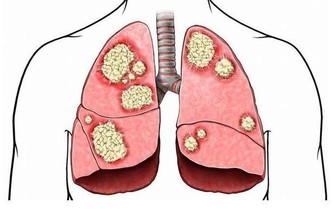

過遲絕經的婦女需要警惕,因為,55歲以後還未絕經,體內激素水平長期偏高,增加了子宮內膜癌和乳腺癌的風險。所以過了55歲未絕經的婦女,必須定期到醫院做B超檢查子宮內膜(有必要時還要做內膜活組織檢查),以及乳腺B超,防患於未然。